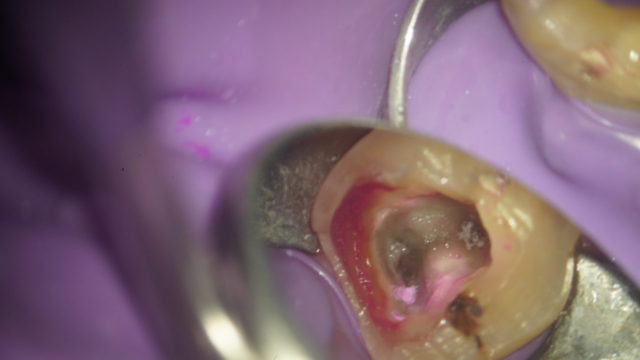

歯の中には神経や血管が入っている細い管、根管があります。虫歯の進行により汚染された神経や、血管などを除去し、内部をきれいに洗浄・消毒してからすき間なく薬剤を充填する処置が根管治療です。

根管内に少しでも細菌を残してしまうと再発してしまいますので、治療には精密さが要求されます。

根管の中は肉眼で見ることができず、従来の治療はレントゲンを参考にしながら、手の感覚を頼りに探り、治療をしていた側面があります。そうすると見落としがおき、感染源が残ってしまい再治療が必要になるケースも出てきます。

マイクロスコープで拡大し、根管内を詳細に観察することで感染源を細部まで取り除き、再発を断ちます。 -

根の治療にはマイクロスコープ(精密な治療をする為の歯科用顕微鏡)とラバーダム(雑菌が入らないようにかけるゴムのシート)を必ず使用して治療します。

根の中にある感染物を全てなくすため、薬液で洗浄して綺麗にします。